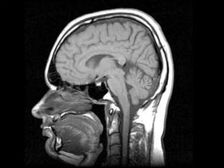

foto da fonti aperte

Gli scienziati di Novosibirsk hanno sviluppato un farmaco che produce il cervello umano per produrre le cellule staminali necessarie per recupero di organi malati. “Il farmaco si riferisce a rigenerativo e non ha analoghi al mondo. Stiamo iniziando quest’anno studi clinici, studi preclinici che abbiamo completato, “- ha affermato il presidente del consiglio di amministrazione e il comproprietario della società, che ha sviluppato il farmaco, Andrei Artamonov. Secondo lui, il farmaco fa sì che il cervello adulto produca nuovo cellule staminali che in seguito trovano un organo danneggiato e ripristinalo. “Nei bambini, il cervello produce attivamente staminali cellule perché il bambino sta crescendo. E il cervello di un adulto capace di produrli, solo lui non vuole farlo – a lui non serve. Il nostro farmaco stimola la produzione del nostro stelo cellule “, ha spiegato Artamonov. Secondo lui, tutte le operazioni con le cellule staminali sono ora prodotte al di fuori del corpo umano comporta un certo rischio associato al fatto che può iniziare una cellula modificata, propagata artificialmente interagire in un luogo inaspettato. Le celle possono essere inserite ma sempre un rischio perché non è molto chiaro dove si trovano differenziato. Sebbene siano tuoi, sono propagati al di fuori del tuo corpo. Le cellule staminali non possono fallire lì differenziarsi. Trovano un organo danneggiato e iniziano questo ripristinare il corpo “, ha aggiunto Artamonov. Prove cliniche il farmaco durerà un anno e mezzo, riferisce Interfax.